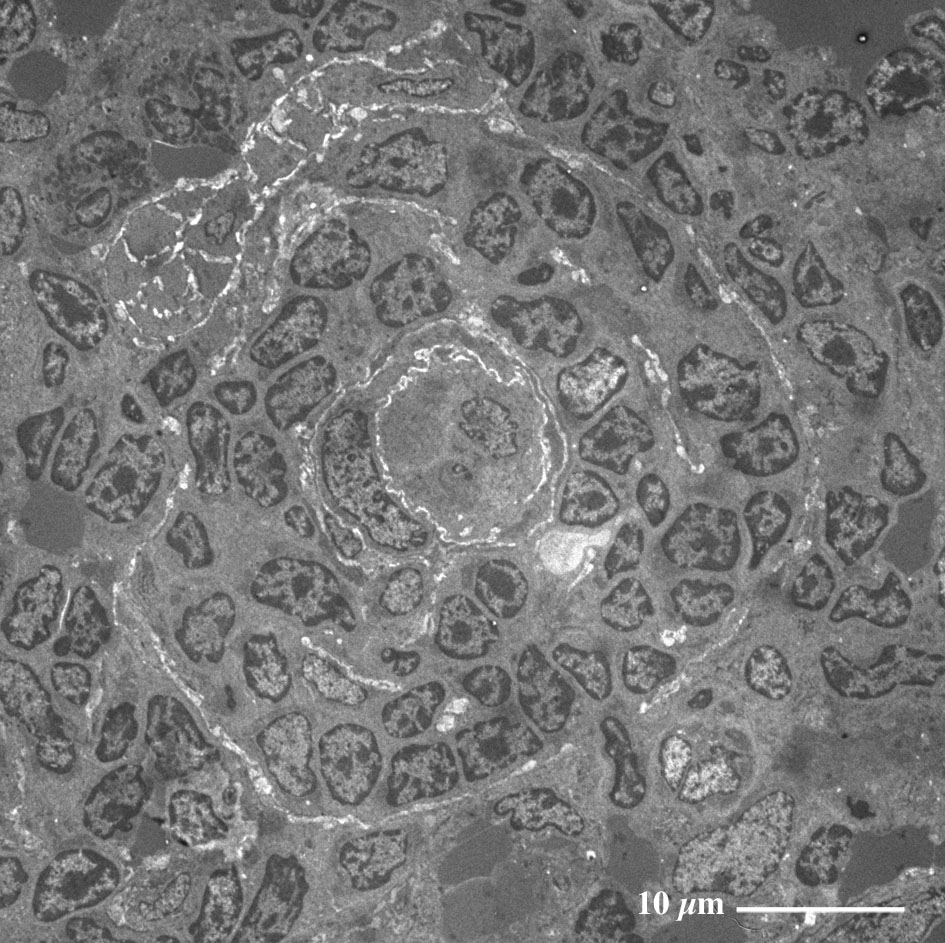

【 薄さ70 - 80 nm 超薄切片の透過型電子顕微鏡画像 】

Transmission electron microscopic image of 70 - 80 nm ultrathin section